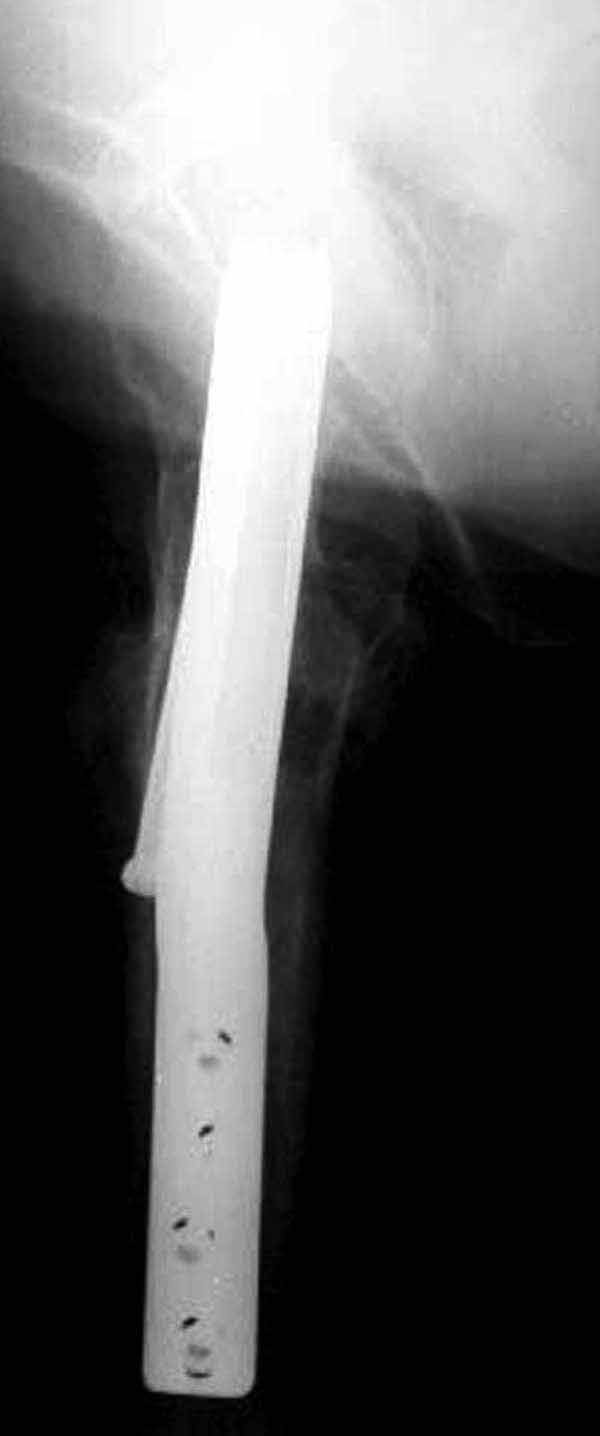

У больных с ожирением и соматическими заболеваниями нежелательно открывать место перелома. Гвозди от DePuy с двумя шурупами рассчитаны для переломов бедра, и приходилось их  применить для фиксации подвертельных переломов, но более адекватную фиксацию создает Gamma 3.

Здесь подобный случай, где стрессовый перелом обнаружен через 2 недели после фиксации. Применен Blade Plate с дополнительными шурупами.